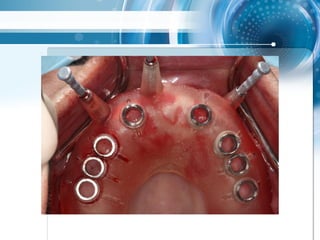

Triple scan Technik

• Multiple Änderungen von Modellsituation nach CT

scan, Extraktionen und Wurzelfüllungen realisiert,

4 geplante Extraktionen

2 mm guide, multiple Extraktionen mit

zahngestütytem drill guide über 3

Zähnen als strategischer Support

Triple scan Technik •Multiple Änderungen von Modellsituation nach CT scan, Extraktionen und Wurzelfüllungen realisiert, 4 geplante Extraktionen

• 58.

2 mm guide,multiple Extraktionen mit zahngestütytem drill guide über 3 Zähnen als strategischer Support